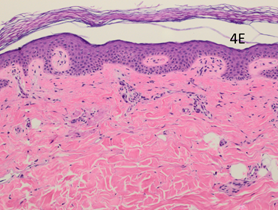

Figure 4E AtPost-RT x 100. Biopsy taken from normal looking infield RT area (position B in Figure 3F). Histopathologically it appears as normal skin.

The post-RT biopsy of the clinically recurrent psoriasis is seen in Figure 4D. This shows the histopathology of the recurrent lesion at eight weeks. The findings of psoriasis are present to a lesser degree than in the pre-RT biopsy. The post-RT biopsy of the clinically normal skin is seen in Figure 4E and shows essentially normal skin whereas, prior to RT, there was florid psoriasis.